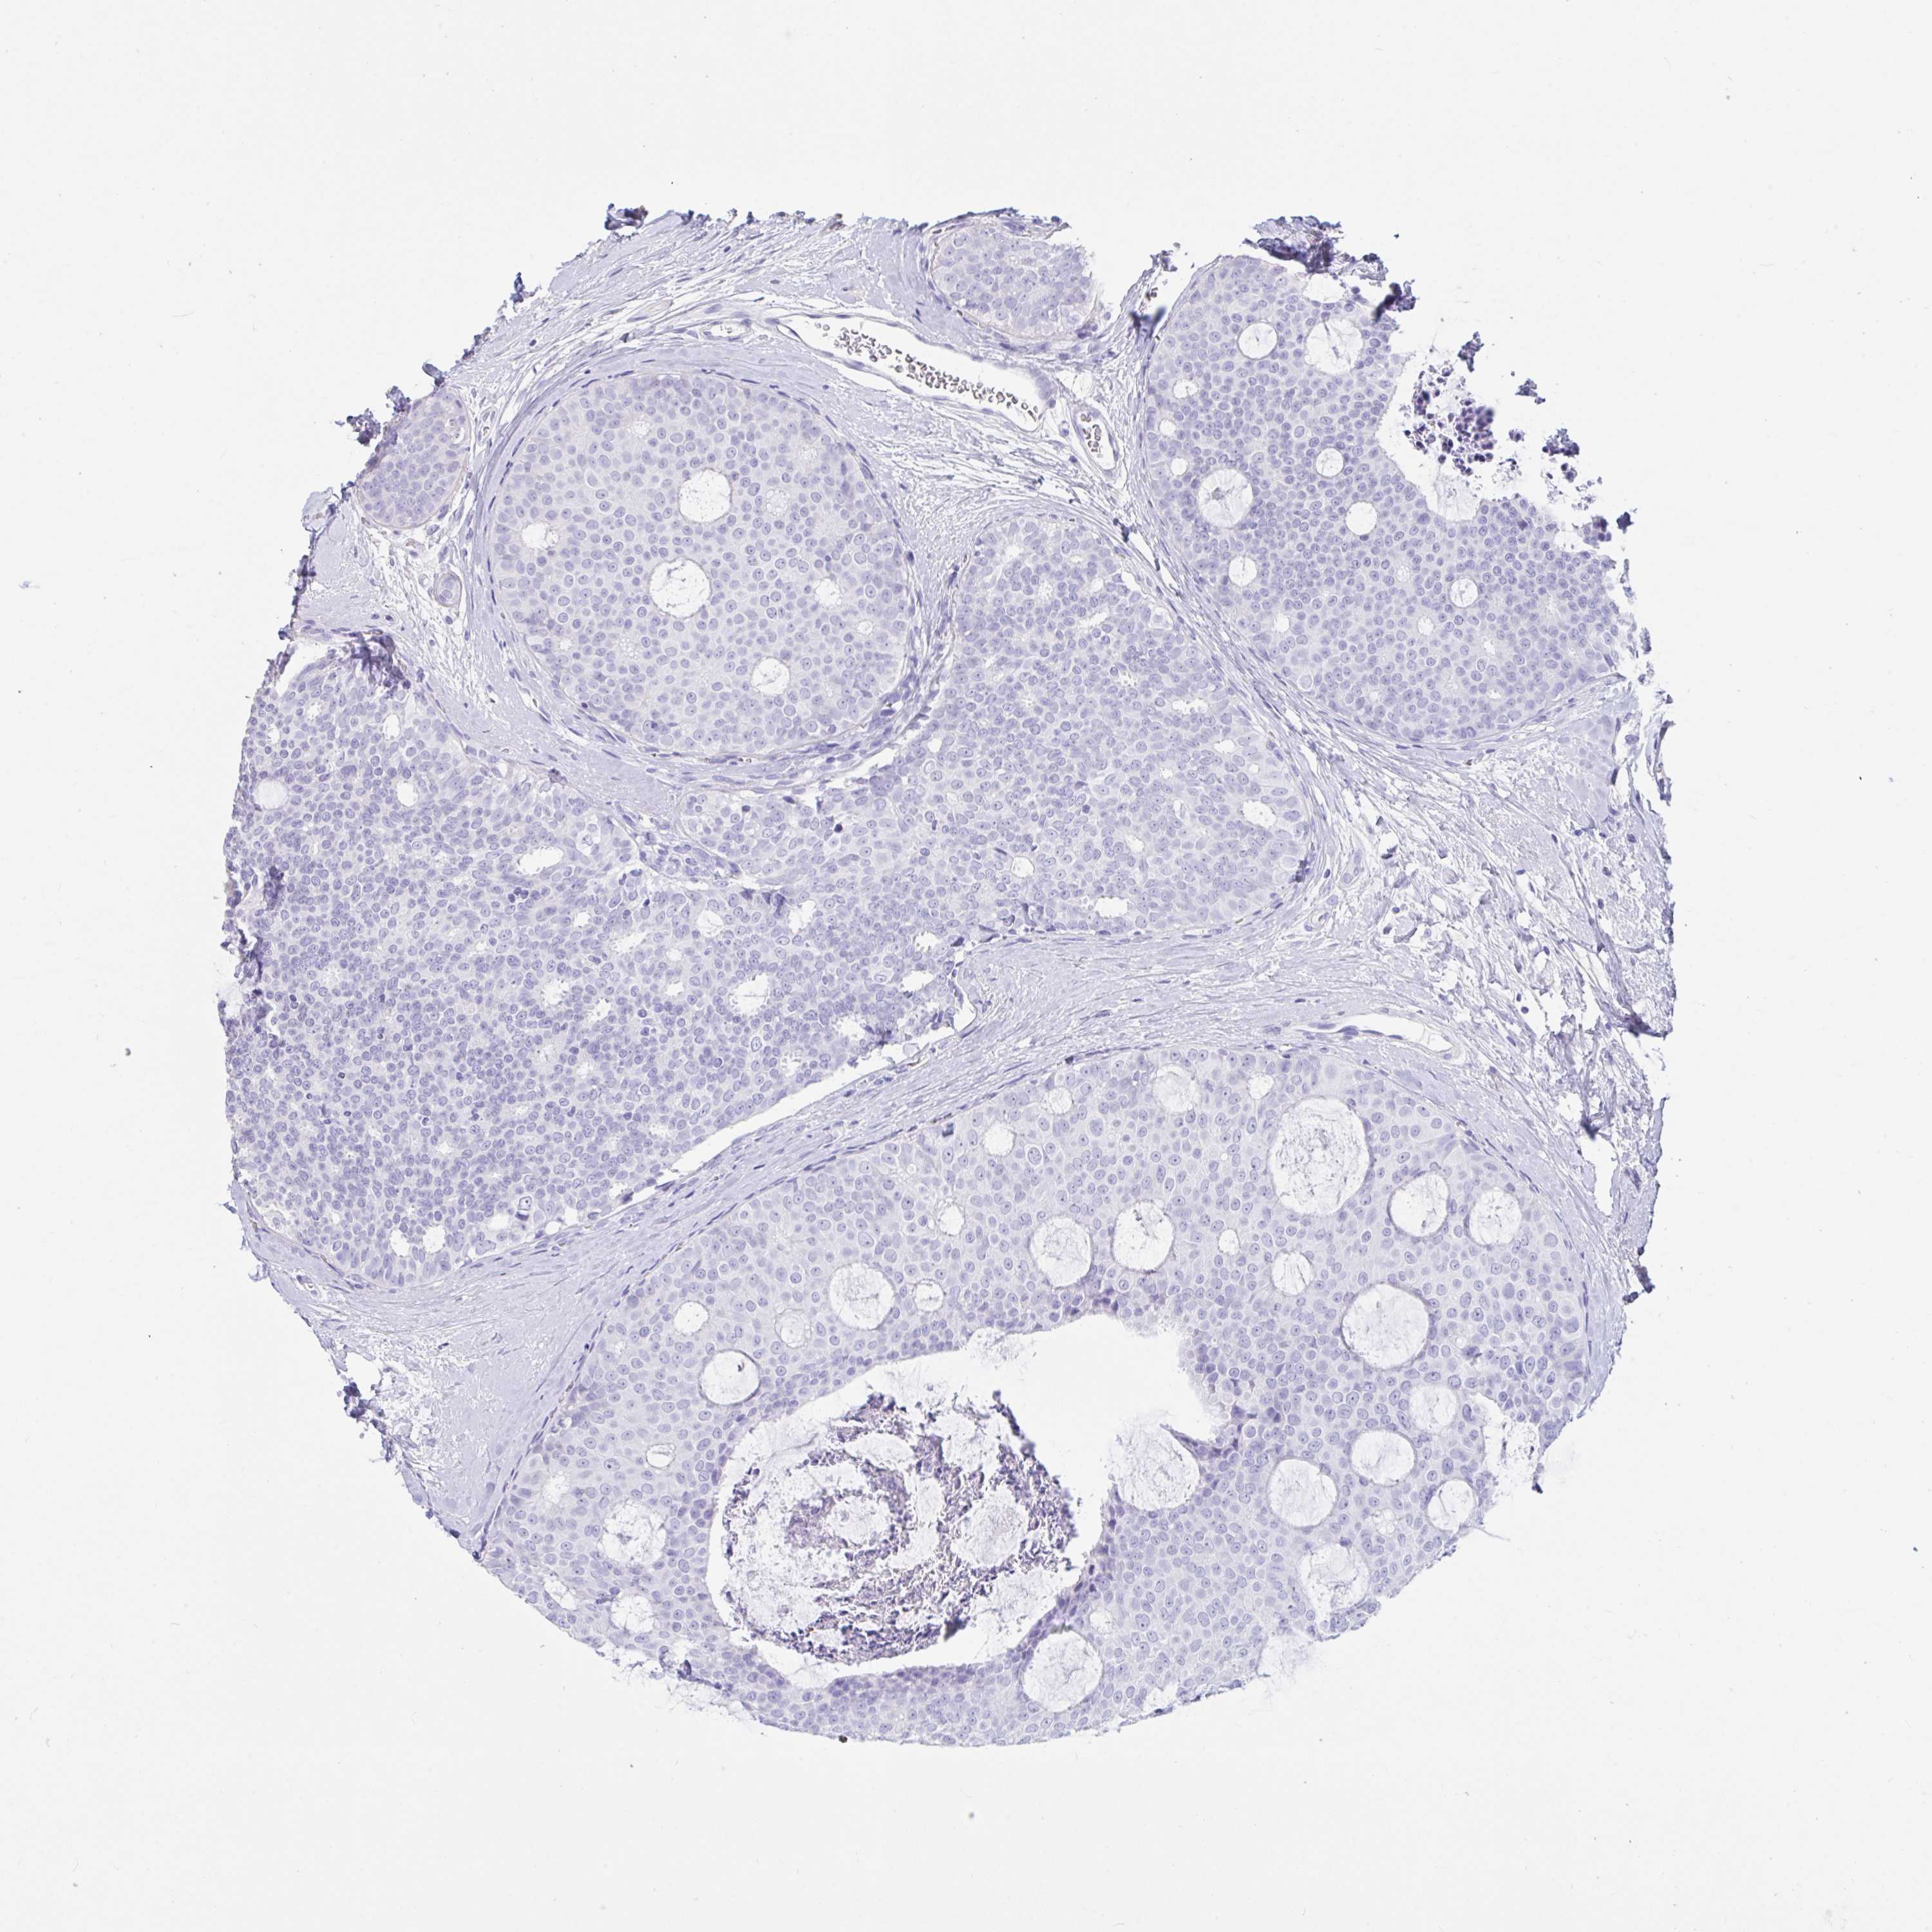

CANCER BREAST CANCER Show tissue menu

BRCA TCGA BRCA VALIDATION PROTEIN EXPRESSION